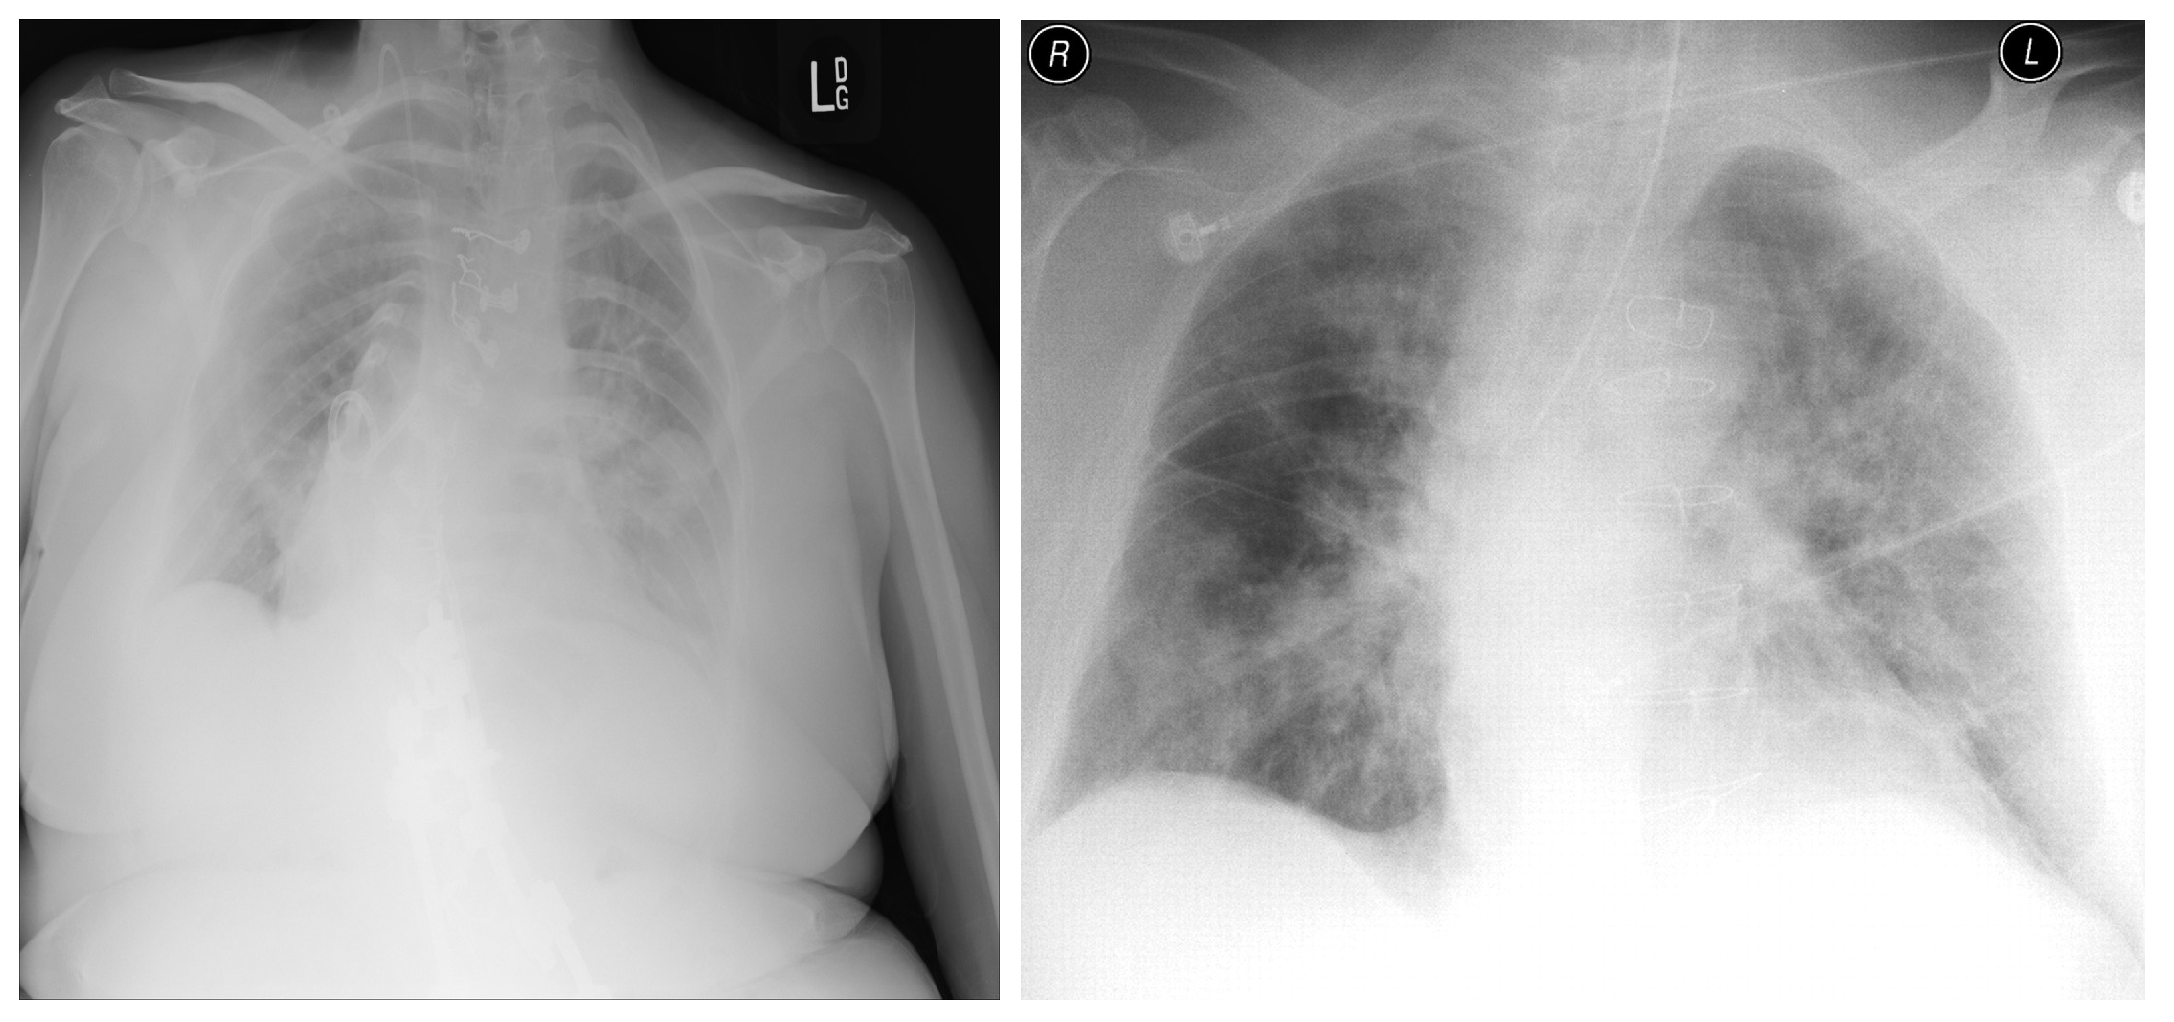

3.8. National Institute of Health (NIH)

3.9. Montfort Dataset

4.1. Data Distribution for Multi-Class and Binary Models